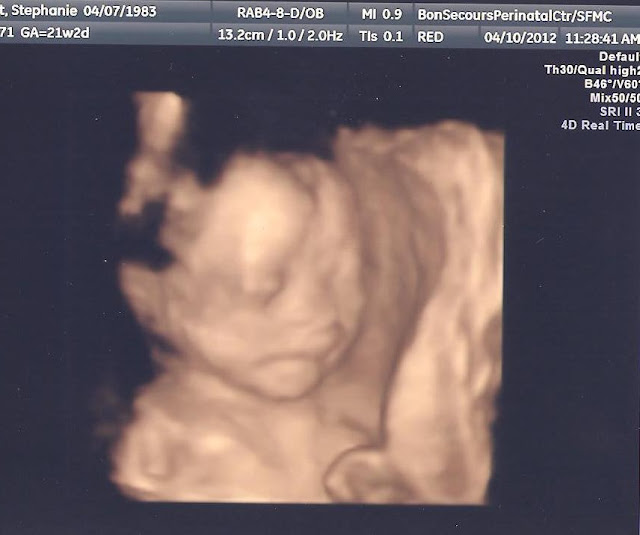

...and here are the 4-D pictures - (we are biased)...but we think she's beautiful!!!

She has her foot near her mouth - look at those toes!